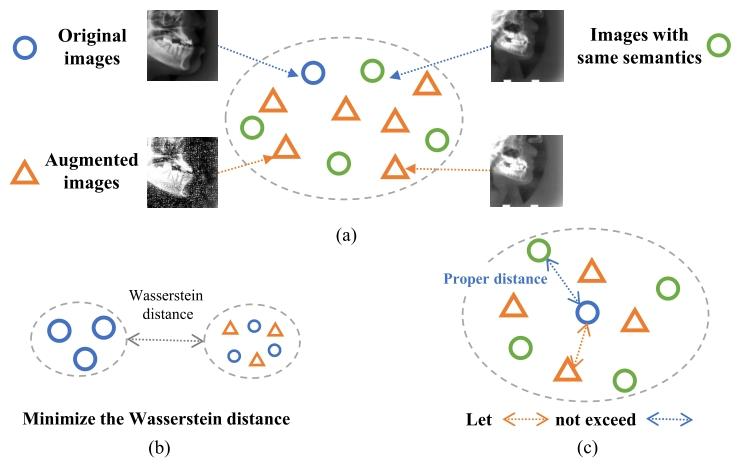

对比学习(CL)相关研究与IGU-Aug策略提出 对比学习(CL)是自监督学习(SSL)的一种形式,在该框架下,数据通过代理任务为模型提供监督信号[2]。与以往的自监督学习方法不同,对比学习的核心是通过对比具有相同分布与不同分布的样本,在嵌入空间中学习数据的特征表示[3]-[7]。目前,对比学习已被广泛应用于提升分类任务(典型的实例级任务)的性能。然而,当将实例级对比学习直接应用于像素级下游任务[8]-[9](如标志点检测、图像分割、目标检测)时,由于监督粒度的差异,其辅助效果十分有限。因此,面临像素级下游任务挑战的研究者更倾向于采用逐像素对比学习。 逐像素对比学习的性能在很大程度上取决于正负样本对的生成质量[10]-[11],这引发了我们对一个关键问题的思考:如何高效地为逐像素对比学习增强训练样本对,尤其是在无监督场景下? 目前尚无针对无监督场景的自动数据增强方法,但Hataya等人在有监督训练中提出的方法为我们提供了启发[1]。该方法将增强参数的搜索转化为增强后数据集与原始数据集的密度匹配问题,认为最优的数据增强应通过生成对抗网络(GAN)[12]减小两个数据集的瓦瑟斯坦距离,从而使二者尽可能相似。然而,由于缺乏标签,该方法无法应用于无监督对比学习,且不适用于逐像素对比学习任务。 本文旨在通过挖掘密集型对比学习的优势与特性,以无监督方式、按像素粒度自适应优化正负样本对的获取,从而解决上述挑战。 首先,图像在像素层面存在信息量不均衡的特点:每个像素及其上下文信息对理解图像中的局部区域、目标物体和整体结构所提供的辅助作用存在差异。例如,在标志点检测这一典型的逐像素任务中,信息量大的像素往往能发挥更重要的作用。因此,对图像中像素的信息量进行量化,并重点关注高信息区域,将对任务性能提升具有重要意义。我们发现,在对比学习中,若对含更多语义信息的像素所构成的正样本对施加过强的增强操作,会对其造成更大损害——过强的增强会给正样本对带来更大的绝对扰动,进而破坏其语义信息。基于此,本文对不同类型的像素采用差异化增强策略:对高信息像素施加较弱的增强,对低信息像素施加较强的增强。但目前鲜有方法能在无监督场景下实现这一目标。为突破这一限制,我们引入图像信息熵(IIE)的概念,用于评估单个像素及其邻域内容的复杂度;借助图像信息熵,我们将像素划分为低信息、中信息和高信息三类,并在信息更丰富的区域内构建更多对比像素对。 其次,对于特定像素,我们可将语义一致的像素归为同一类别。随后,与以往方法类似,我们通过观察增强后数据与原始数据的兼容性,来评估数据增强参数的适用性。在实际操作中,我们通过判断增强后数据中边缘样本到中心样本的距离是否超出合理范围,来确定数据增强的适宜性(需注意,该距离通过互信息进行估计)。此外,若为每个像素单独估计增强参数,会引入显著误差,因此我们采用组级平均的方式来降低这种误差。图1直观展示了本研究思路的核心动机。 综上,我们提出一种面向逐像素对比学习的信息引导式像素增强(IGU-Aug)策略,其主要贡献如下: 1. 据我们所知,本文首次提出按像素粒度设计的像素增强方法,用于改进无监督逐像素对比学习。 2. 引入图像信息熵(IIE) 这一指标来量化单个像素所含的信息量;以图像信息熵值为指导,将像素划分为低信息、中信息和高信息三类,并验证了中高信息像素在逐像素对比学习中的重要性。 3. 以无监督方式为不同类别像素设计自适应增强强度,显著提升了实验性能。 4. 通过大量实验验证了核心策略(包括偏向性选择高信息像素、采用自适应增强策略)的有效性:在头影测量数据集和手部X射线数据集上,将单样本模型CC2D[13]的平均重建误差(MRE)分别从2.85mm降至2.31mm、从2.20mm降至1.70mm;此外,该策略还显著提升了腹部磁共振(Abd-MRI)和腹部计算机断层扫描(Abd-CT)数据集上的单样本分割模型性能。

Fig. 1. (a) Similar to [1], we regard data augmentation as a process thatfills missing data points of the original training data; (b) Hayata et.al [1]minimize the Wasserstein distance between original and augmenteddatasets by GAN trained with labeled samples; © Our method estimatesa reasonable distance by finding samples of the same class and controlsthe augmented samples within the distance

图1 数据增强思路对比 (a)与文献[1]的思路类似,本文将数据增强视为对原始训练数据中缺失数据点的补充过程; (b)Hayata等人[1]通过利用带标签样本训练生成对抗网络(GAN),最小化原始数据集与增强后数据集之间的瓦瑟斯坦距离; (c)本文方法通过寻找同类样本估计合理距离范围,并将增强后的样本控制在该距离范围内。